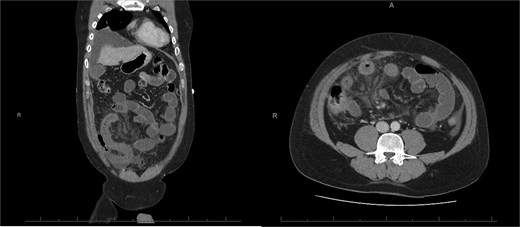

A 45-year-old male presenting with a 10-day history of isolated right lower quadrant (RLQ) abdominal pain. His history included deep vein thrombosis, coronary artery disease with prior STEMI, left anterior descending artery stenting in 2014, and ongoing antiplatelet therapy with aspirin. Upon admission, RLG tenderness was noted. Laboratory revealed leucocytosis (WBC 16 G/L) and elevated CRP (70 mg/L). E-CT revealed superior mesenteric and portal systems thrombosis with ischemia of a small bowel loop in the RLQ, characterized by absent bowel wall enhancement and free fluid (Fig. 4). Besides these findings, he was managed conservatively with a UFH bolus of 5000 U/l, followed by a continuous infusion of 36 000 U/l over 24 h (target INR 0. 35–0. 7), Ceftriaxone and Metronidazole, bowel rest, and ICU monitoring for 48 h. Clinical and biological improvement was rapid. E-CT on the second day showed no signs of perforation (Fig. 5). He was discharged after 7 days on LMWH (enoxaparin sodium 90 mg every 12 h). Twenty days later, he re-presented with acute RLQ pain and localized peritonism. E-CT revealed a covered perforation of the previously ischemic small bowel loop (Fig. 6). A segmental bowel resection with primary anastomosis was performed by laparotomy (Fig. 7). The postoperative course was uneventful, and he was discharged on postoperative day 4 with sodium enoxaparin 90 mg/12 h.

E-CT in the second patient at admission. White arrows showing porto-mesenteric thrombosis. Dashed arrows indicate a portion of small bowel loop ischemia in the right lower quadrant characterized by the absence of bowel wall enhancement and free fluid.